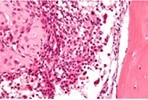

Figure 1.Chondroblastoma demonstrating round to oval chondroblastic cells with abundant, eosinophilic cytoplasm and vesicular grooved nuclei encompassed within a myxochondroid matrix5.

Chondroblastoma demonstrating round to oval chondroblastic cells with abundant, eosinophilic cytoplasm and vesicular grooved nuclei encompassed within a myxochondroid matrix5.

Upon microscopy, tumefaction is significantly cellular and composed of sheets of spherical to polyhedral chondroblastic cells imbued with abundant, eosinophilic cytoplasm and well demarcated cellular perimeter. Intracytoplasmic glycogen granules are evident. Nuclei appear elliptical, hyper-lobulated and demonstrate nuclear grooves. Nuclear atypia appears insignificant 1, 2.

Focal aggregates of spindle-shaped cells may be enunciated. Peri-cellular zones of ‘lace-like’ or ‘chicken wire’ calcification appear intermingled with degenerative chondroblasts. Eosinophilic foci of chondroid matrix are invariably discerned 1, 2.

Focal mitotic activity, necrosis and osteoclast-like giant cells may be commingled with cellular zones. Besides, aneurysmal bone cyst-like modifications are commonly observed 1, 2.